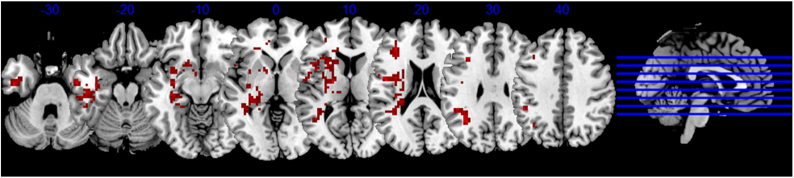

The epidemic of coronavirus disease 2019 (COVID-19) has broken the normal spread mode of respiratory viruses, namely, mainly spread in winter, resulting in over 230 million confirmed cases of COVID-19. Many studies have shown that severe acute respiratory syndrome coronavirus-2 (SARS-CoV-2) can affect the nervous system by varying degrees. In this review, we look at the acute neuropsychiatric impacts of COVID-19 patients, including acute ischemic stroke, encephalitis, acute necrotizing encephalopathy, dysosmia, and epilepsy, as well as the long-term neuropsychiatric sequelae of COVID-19 survivors: mental disorder and neurodegenerative diseases. In particular, this review discusses long-term changes in brain structure and function associated with COVID-19 infection. We believe that the traditional imaging sequences are important in the acute phase, while the nontraditional imaging sequences are more meaningful for the detection of long-term neuropsychiatric sequelae. These long-term follow-up changes in structure and function may also help us understand the causes of neuropsychiatric symptoms in COVID-19 survivors. Finally, we review previous studies and discuss some potential mechanisms of SARS-CoV-2 infection in the nervous system. Continuous focus on neuropsychiatric sequelae and a comprehensive understanding of the long-term impacts of the virus to the nervous system is significant for formulating effective sequelae prevention and management strategies, and may provide important clues for nervous system damage in future public health crises.